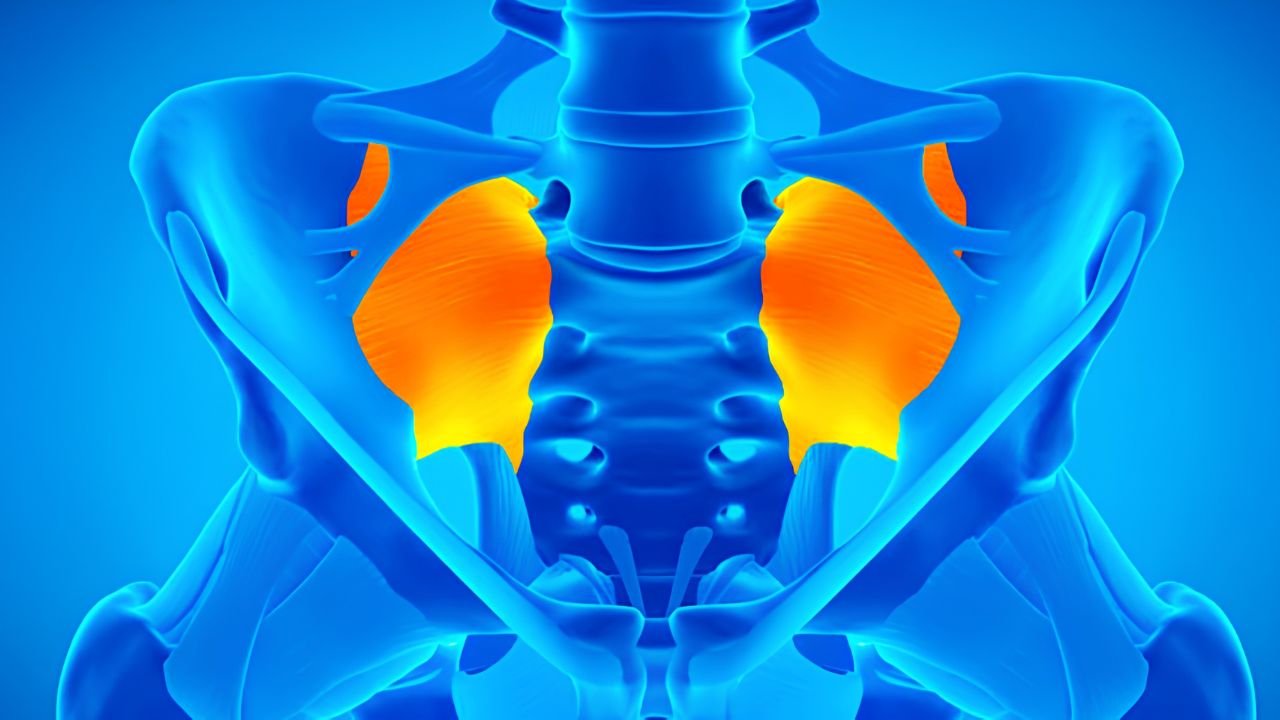

A sacroileíte é uma inflamação na articulação sacroilíaca, que conecta a base da coluna vertebral (sacro) à bacia (ílio). Essa

A sacroileíte é uma inflamação na articulação sacroilíaca, que conecta a base da coluna vertebral (sacro) à bacia (ílio). Essa

A sacroileíte é uma inflamação na articulação sacroilíaca, que conecta a base da coluna vertebral (sacro) à bacia (ílio). Essa

A sacroileíte é uma inflamação na articulação sacroilíaca, que conecta a base da coluna vertebral (sacro) à bacia (ílio). Essa